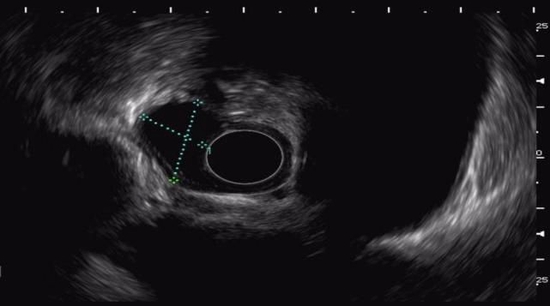

检查中发现食管隆起性病变,考虑来源于管壁深层。为进一步明确诊断,消化内科韩霜主任为患者实施了超声胃镜检查。结果提示为固有肌层肿瘤,考虑平滑肌瘤的可能。

超声内镜提示为固有肌层低回声病变